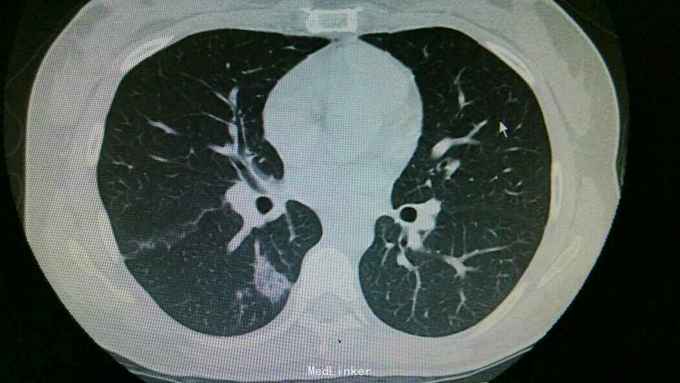

查体:双肺呼吸音粗,右肺可闻及湿罗音, 余无特殊 辅查:血常规示中性粒细胞稍高。胸片:右上肺野炎性病变。肺炎支原体抗体滴度1:640。胸部CT:双肺炎症。

诊断:支原体肺炎。 治疗,予以阿奇霉素抗感染,止咳化痰等处理。复查胸片提示炎症较前好转。

讨论+随访:临床支原体肺炎为不典型肺炎,其诊断主要依靠支原体抗体滴度及影像学检查。一般治疗一个星期可好转。